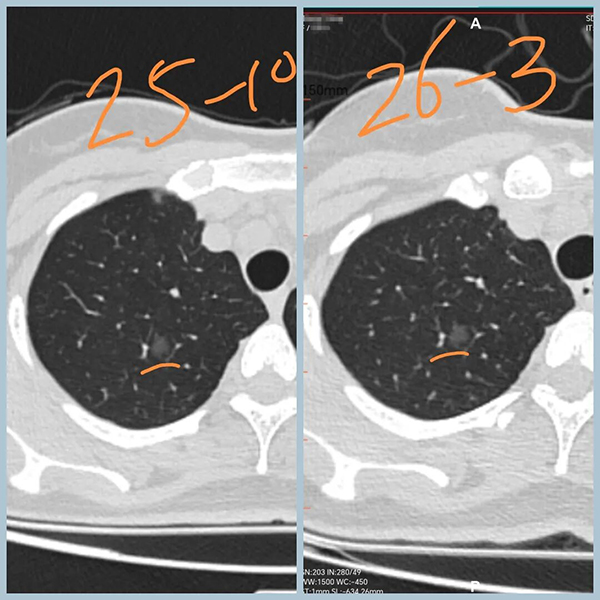

女性,30+,发现双肺结节5个月

分别是右肺上叶纯磨玻璃结节,大小约8mm

左肺下叶实性结节,大小约1cm

5个月后复查,右肺磨玻璃结节无变化,左肺实性结节增大